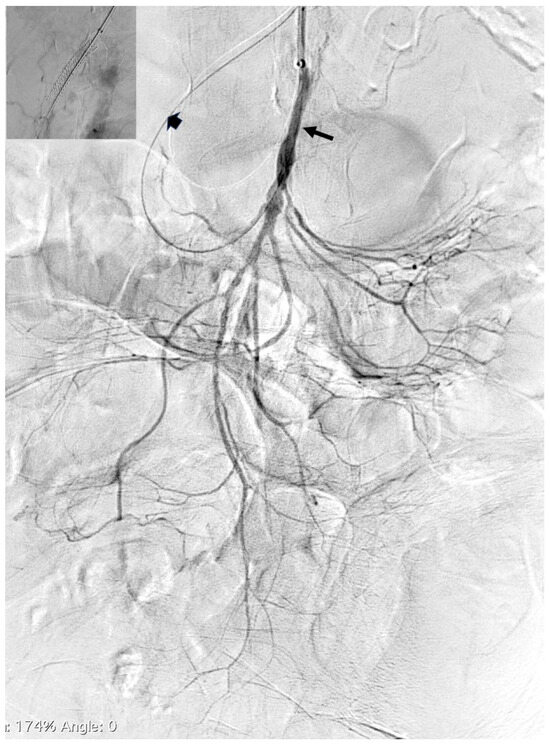

After predilation, there was a good inflow to the SMA and its branches (Figure 3). Finally, the 6.0/38 mm Omnilink Elite balloon-expandable stent (Abbott Vascular, Abbott Park, IL, USA) was implanted in the proximal part of the SMA. After stent implantation, there was a brisk inflow to the target artery and its branches.

Figure 3.

Catheter angiography after predilation of the proximal part of the superior mesenteric artery (black arrow), good inflow to this artery and its branches, thick arrow points the guidewire navigated through the branches of the celiac trunk; in the left upper corner of the picture after stent implantation.